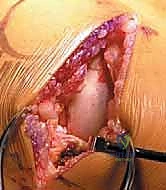

صورة طبية: استبدال مفصل الركبة الجزئي (UKA): دليل شامل لمرضى خشونة الركبة الداخلية مع الأستاذ الدكتور محمد هطيف